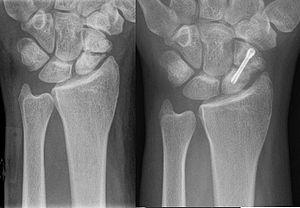

Scaphoid pseudarthrosis before and after surgical fixation

Surgery

Surgical treatment options include:

• Removal of all scar tissue from between the fracture fragments

• Immobilization of the fracture with internal or external fixation. Metal plates, pins, screws, and rods, that are screwed or driven into a bone, are used to stabilize the broken bone fragments.

• Bone grafting. Donor bone or autologous bone (harvested from the same person undergoing the surgery) is used as a stimulus to bone healing. The presence of the bone is thought to cause stem cells in the circulation and marrow to form cartilage, which then turns to bone, instead of a fibrous scar that forms to heal all other tissues of the body. Bone is the only tissue that can heal without a fibrous scar. Autologus bone graft is the "gold standard" treatment of the non union the bone is obtained from the iliac crest.